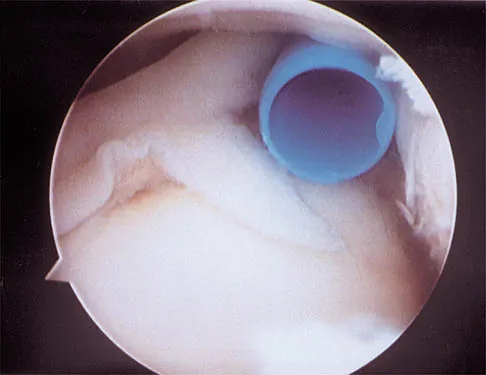

A 15-year-old wrestler sustains an abduction, hyperextension, and external rotation injury to his right shoulder. The MRI scan findings shown in Figures 27a and 27b are most consistent with

Explanation